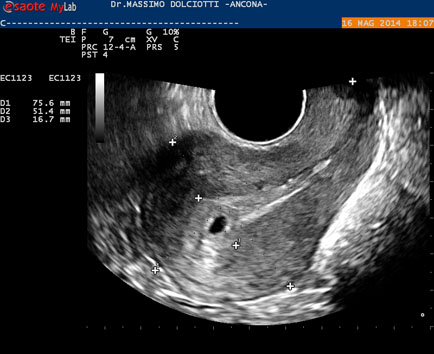

Data inserimento: 19 /05/2014Ecografia del: 16/05/2014 Strumento: Esaote MyLab 50 Gold - Responsabile Linea Cardio Esaote Regione Marche Dr. Franco Fabi Sonda: Endocavitaria Multifrequenza 4-8 MHz Età Paziente: F 27 anni Motivazione dell'esame: amenorrea. Beta HCG = 1.459 mUI/ml. Commento all'esame: le immagini ed il video documentano utero retroverso, con endometrio ispessito e presenza del sacco gestazionale delle dimensioni di 7,6 x 7,2 mm. All'ovaio destro presenza di corpo luteo gravidico con vascolarizzazione aumentata. Conclusioni: gravidanza alla quarta settimana di gestazione (Pregnancy at the fourth week of gestation). Potete esprimere le vostre osservazioni e commenti sul BLOG. Presentazione: Dr. Massimo Dolciotti - Ancona Elaborazione digitale: Andrea Dini - Ancona